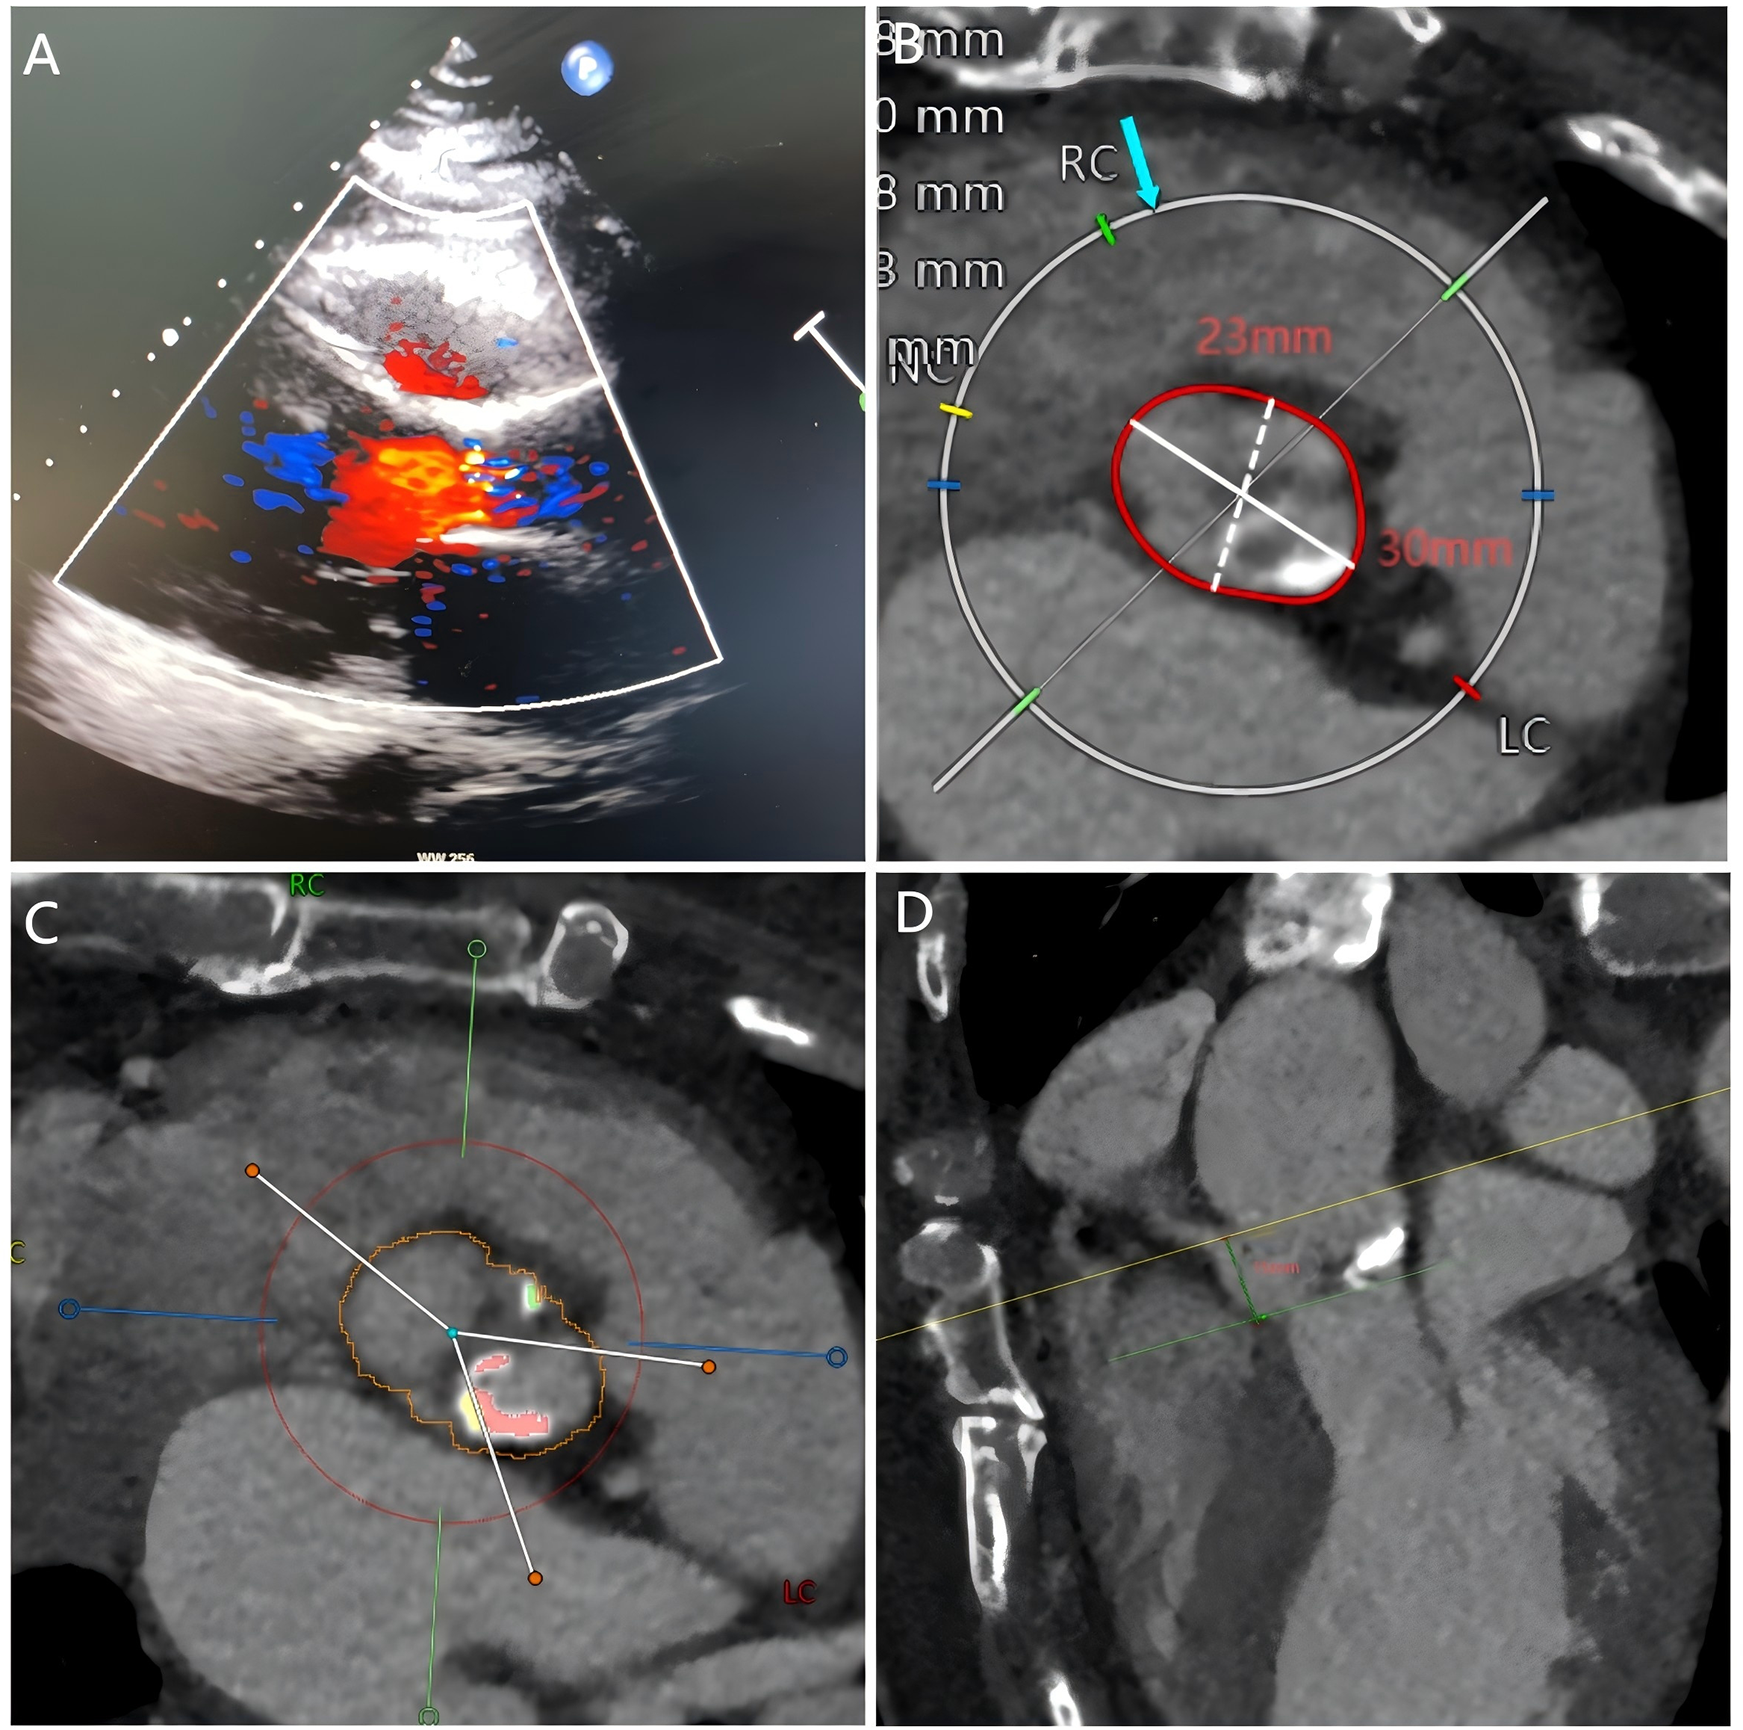

Figure 1

Echocardiography and cardiac computed tomography prior to TAVR. (A) Echocardiography showed severe aortic stenosis. (B–D) Pre-TAVR CT showed the aortic annulus diameter, calcified bicuspid aortic valve, and the position of the right coronary artery.

The selection of a 23 mm Taurus self-expanding valve (1) was based on pre-TAVR CT (Figures 1B–D) and transesophageal echocardiography (TEE) findings. With active root imaging assistance and pigtail catheter positioning assessment, successful deployment of the valve within the aortic annulus was achieved. Unfortunately, the valve was deployed too high, and acute obstruction of the right coronary artery (RCA) was observed through TEE and radiography subsequent to valve deployment (Figure 2A). Hypotension and pulseless electrical activity necessitated sustained cardiopulmonary resuscitation.